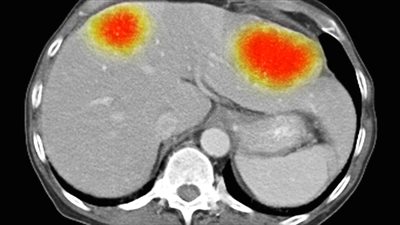

مرض حمى التيفود عدوى بكتيرية يمكن أن تنتشر في جميع أنحاء الجسم، وتؤثر على العديد من الأعضاء، وبدون علاج سريع، يمكن أن يسبب مضاعفات خطيرة ويمكن أن يكون مميتًا بحسب موقع "NHS" الطبي.

وينتج مرض حمى تيفود عن بكتيريا تسمى السالمونيلا التيفية، وهي مرتبطة بالبكتيريا المسببة للتسمم الغذائي بالسالمونيلا.